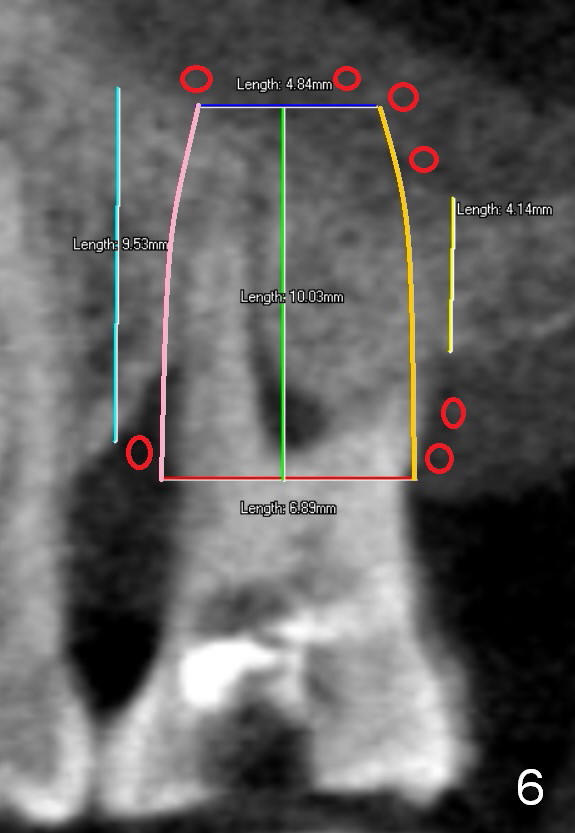

Two years post RCT, there is radiolucency around the MB root of the tooth #3 (Fig.1,2). Eleven days later, there is acute infection associated with MB and DB root fracture (Fig.3). According to the X-ray taken 11 days earlier (Fig.1,4), a long tissue-level implant (6x17 mm) is suitable for the site. In accordance with CBCT (coronal (Fig.5) and sagittal (Fig.6) sections) taken prior to RCT, a short bone-level implant (6.9x10 mm) is a more reasonable choice.

After extraction, the socket will be studied to determine where the bone is and where bony defects are for the site of the initial osteotomy. Start with 2 mm pilot drill or RT2, apparently ~ 6 mm depth, followed by reamers 2.5-3.5 mm and Tatum taps 4.5-7x17 mm (14 mm depth from gingival margin). Use a latch adapt with the torque wrench. Due to severe bone loss, the tap should not be too large (6 mm). If insertion torque is high and bone morphology is favorable, change to DIO taps and take necessary PAs to decide the length of the implant relative to the sinus floor and trajectory. If the depth is 10 mm or less, use SM; 12 mm UF. Based upon the most recent X-ray (Fig.3 with large lesion), the implant should be large and long (Fig.7: 7x17 mm).